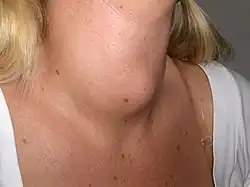

Körperliche Untersuchung

Erkrankungen der Schilddrüse können oft bereits mittels körperlicher Untersuchung erkannt werden. Eine ausgeprägte Struma oder eine obere Einflussstauung sind meist sichtbar (Inspektion). Narben im Halsbereich können Anlass sein, die Anamnese bezüglich Voroperationen zu ergänzen. Beim Morbus Basedow ist auf Zeichen einer endokrinen Orbitopathie zu achten: Exophthalmus, Rötung und Schwellung der Lider und Bindehäute.

Die Schilddrüse kann durch Abtasten (Palpation)[1] untersucht werden. Hierzu wird der Hals des Patienten – meist im Sitzen – von vorne oder von hinten mit beiden Händen abgetastet. Neben der Größe beider Schilddrüsenlappen und des Isthmus (der Gewebebrücke zwischen beiden Lappen) interessiert auch ihre jeweilige Beschaffenheit. Eine harte Schilddrüse findet sich bei der Riedel-Struma und bei bösartig verändertem Organ. Druckschmerzhaftigkeit spricht für eine subakute granulomatöse Thyreoiditis oder einen Abszess. Größe und Lage von Schilddrüsenknoten sollen erfasst werden. Fehlende Verschieblichkeit der Gesamtschilddrüse oder von Schilddrüsenknoten beim Schlucken weist auf bösartige Veränderungen hin. Bei der Palpation der übrigen Halsweichteile können vergrößerte Halslymphknoten ein Hinweis wiederum auf ein Malignom oder aber auf eine Entzündung der Schilddrüse sein.